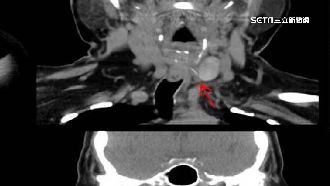

▲醫生在男嬰食道中夾出洩氣的氣球。(示意圖)

男嬰在家本來好端端的,突然呼吸困難,送醫搶救後,醫生在男嬰的食道中夾出一個洩氣的氣球。原來是白天的時候,夫妻倆帶著孩子去參加其他小朋友週歲慶生活動,現場有用氣球佈置,可能是有氣球破掉的碎片被男嬰抓到,在大人都沒注意的情況下吃進肚子裡。